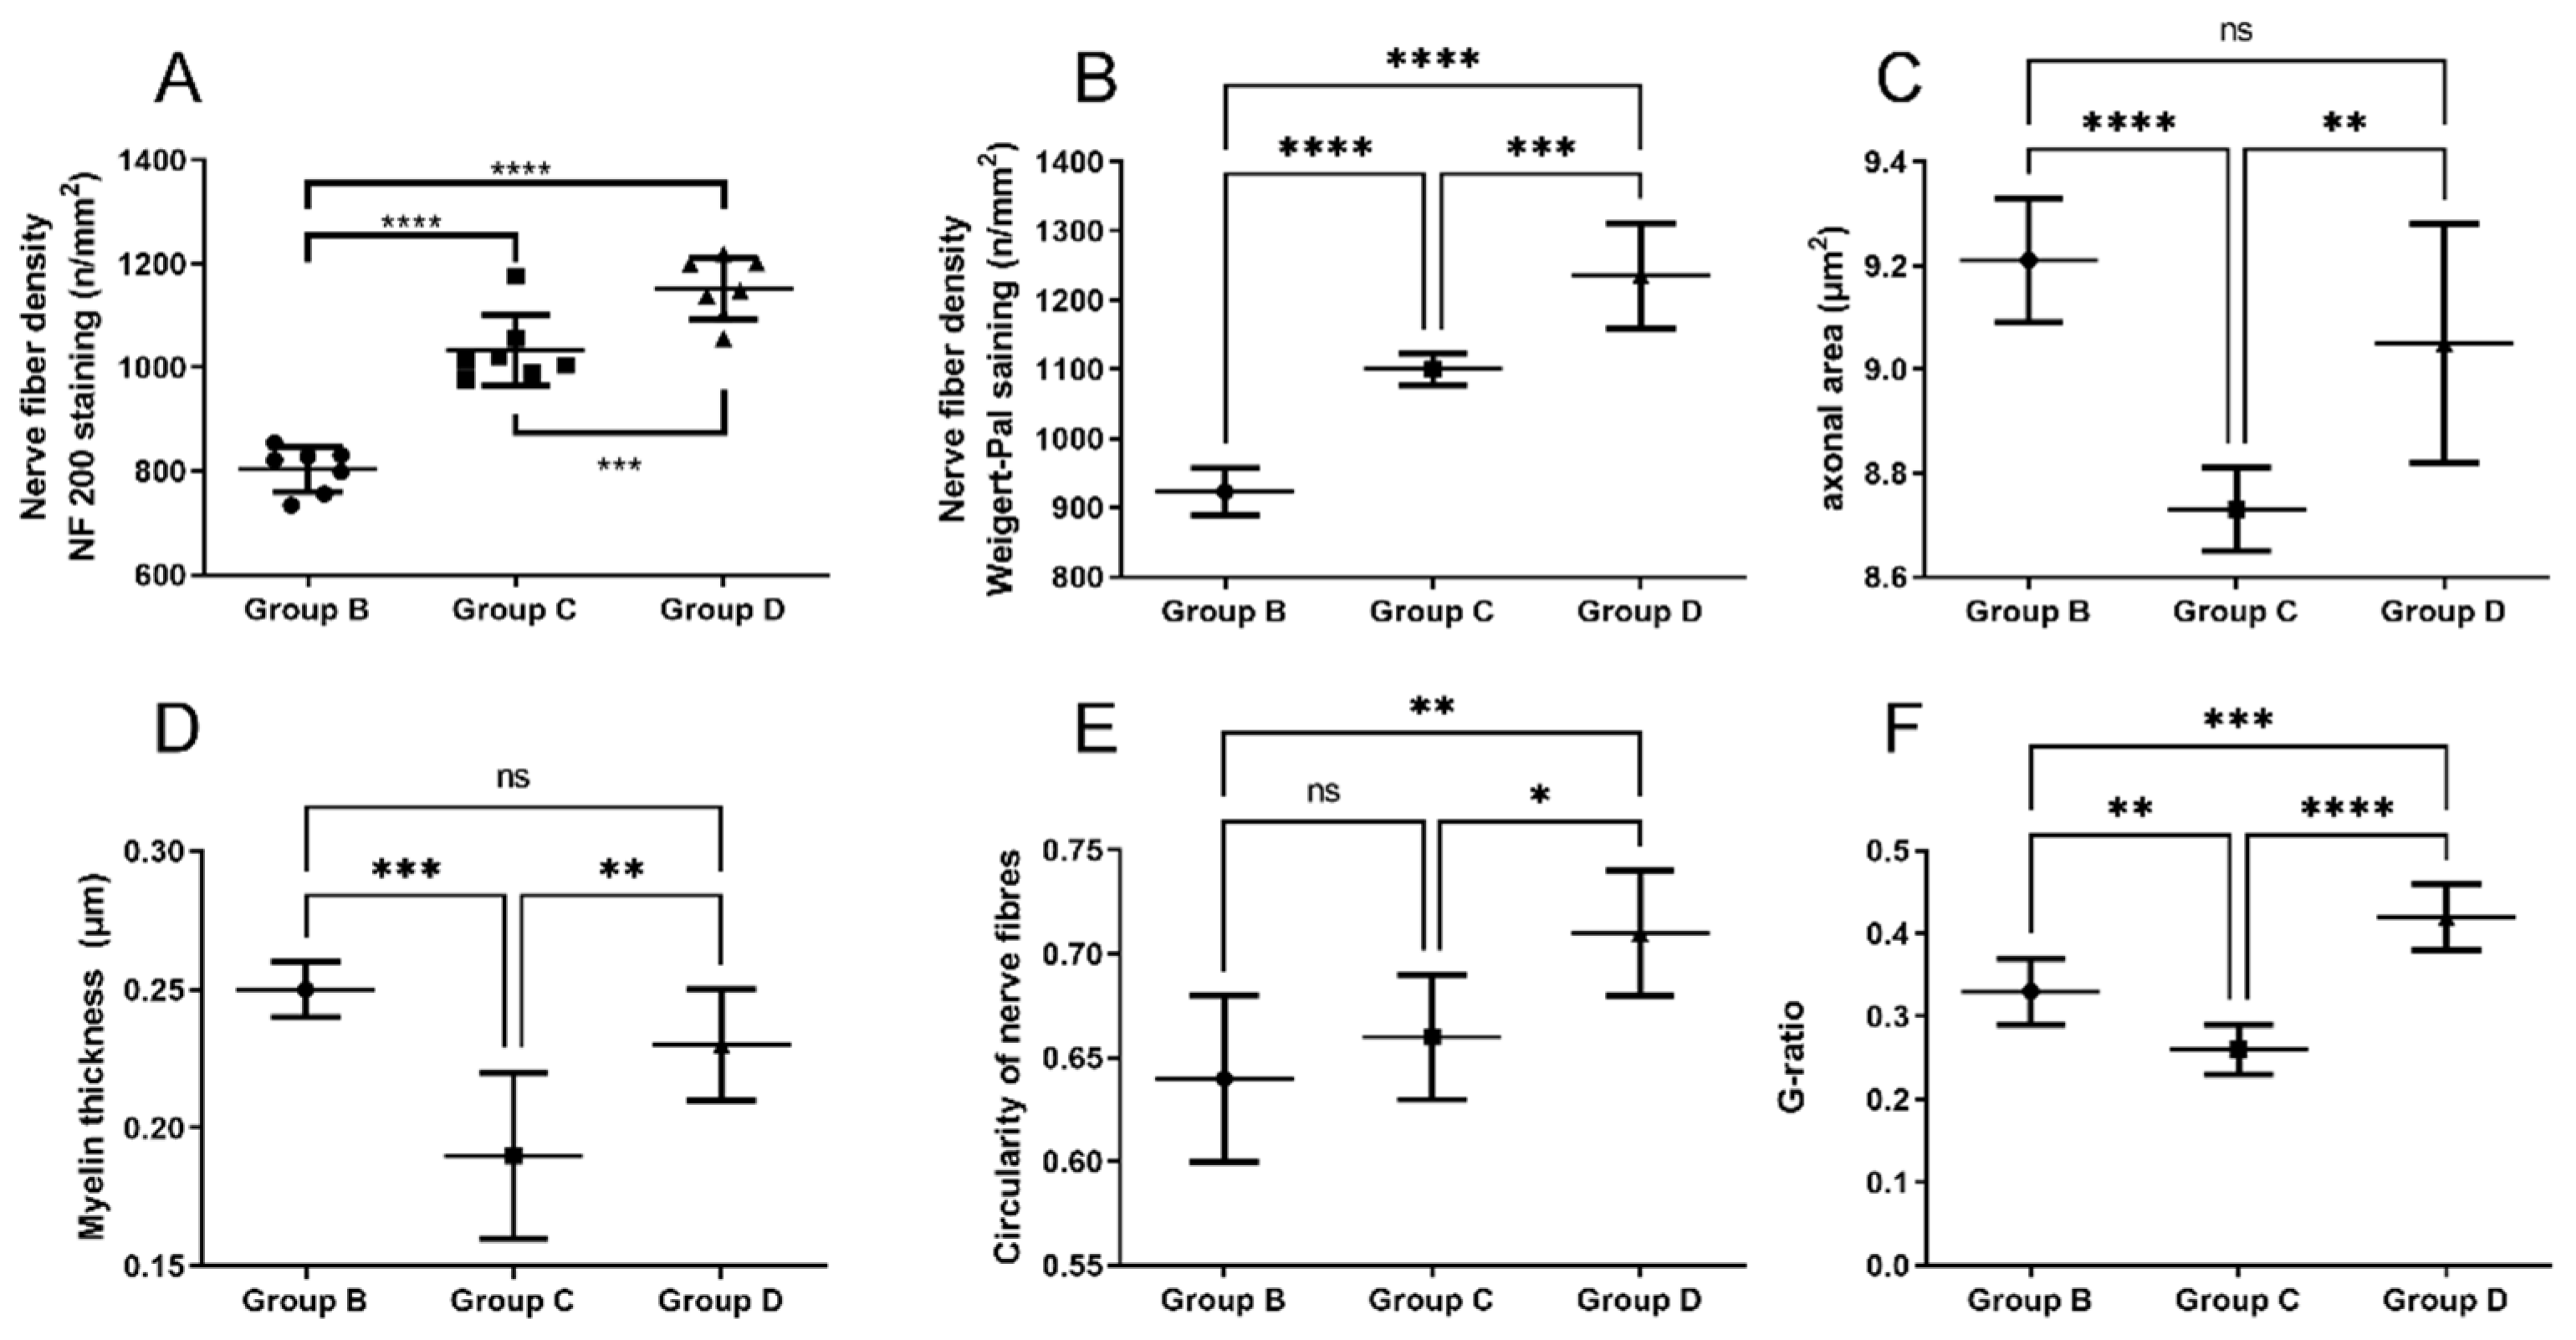

2.5. Neural Tissue